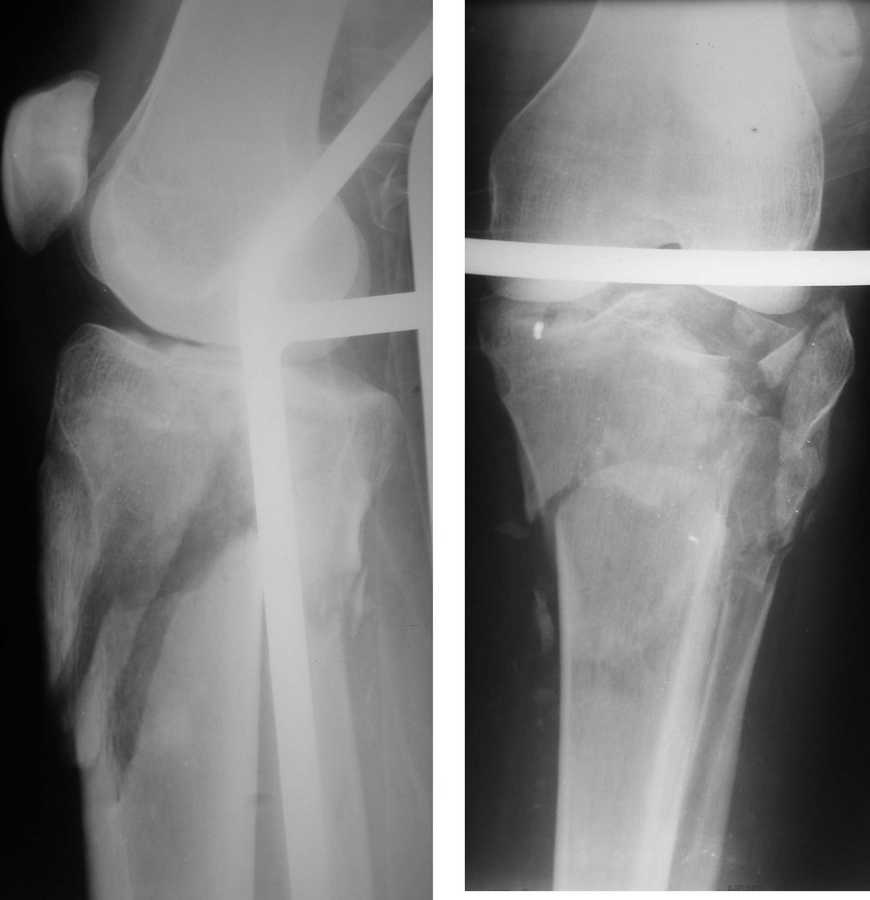

Саша, а в чем конкретно неясность? Надо полагать, вопрос не про общие принципы лечения переломов типа Schatzker VI или C3 по классификации AO, которые можно найти в любом руководстве?

Очаг некроза 4 на 5 см по передней поверхности голени не оставил никакого варианта кроме внешнего остеосинтеза.

Но решили делать в 2 этапа. Первый - восстановить ось и дать костной крошке в проксимальном отделе консолидироваться.

Второй - собственно артродез.

Но по результатам первого этапа думаем дать пациенту попользоваться ногой. А там посмотрим.

Для первого этапа достаточно. Через 5-10 дней мы бы приступили к следующему этапу. А именно, фиксация из ограниченного заднемедиального доступа 1\3 трубчатой или рекон пластиной медиального фрагмента, и остеосинтез наружного мыщелка из второго тоже ограниченного латерального доступа без артротомии, под контролем ЭОПа..... Сухой некроз в данном случае не являлся бы серьезной помехой для внутренней фиксации (во всяком случае, судя по имеющимся фото)

Я думаю, это не повод сразу думать об артродезе... Конечно уже прошло много времени. Но до месяца у нас есть опыт вполне удачных реконструкций и "переделок"...

Оставляя внутрисуствной перелом в таком положении с замкнутым суставом, вы практически обрекаете пациента...IMHO

P.S. безусловно, с двумя пластинами LCP, каннюлироваными винтами, хроносом все это дорого... Но того же анатомического и функционального результата можно достичь, используя вместо пластин аппарат Илизарова, и разрезы для репозиции тогда нудны совсем маленькие .